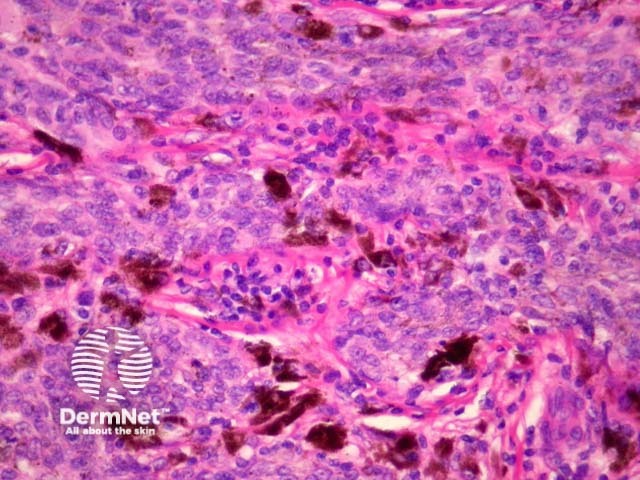

Cutaneous metastasis of melanoma can cause diagnostic confusion. The metastatic melanoma may invade the dermis or subcutis and form a nodular tumour mass without invasion of the overlying epidermis (figure 1). The pattern of growth may mimic a benign intradermal naevus at low power (figure 1) but at high power examination the nuclear atypia is usually obvious, there may be mitoses and there is minimal evidence of maturation (decrease in cell size) with descent in the dermis (figure 2). Usually the lack of epidermal involvement is a good clue the tumour is a metastasis from another site but sometimes the metastasis may invade the epidermis and closely simulate a primary melanoma.

Rarely, melanoma which has metastasised to the dermis may closely mimic a blue naevus (blue naevus-like melanoma, figures 3,4). This can cause considerable diagnostic difficulty and be impossible to correctly recognise without clinical information.

Figure 1

Figure 2

Figure 3

Figure 4